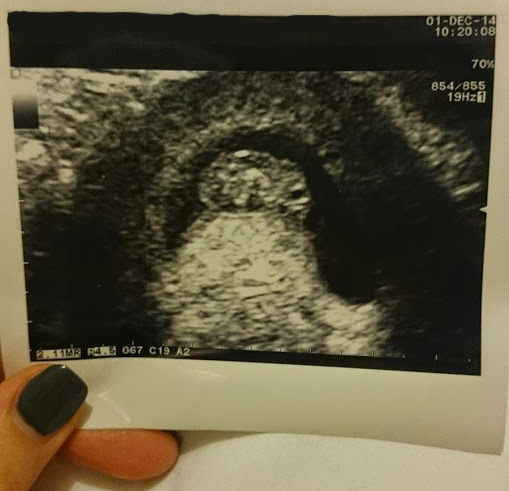

yay! lovely pic miseskimo exciting!!!